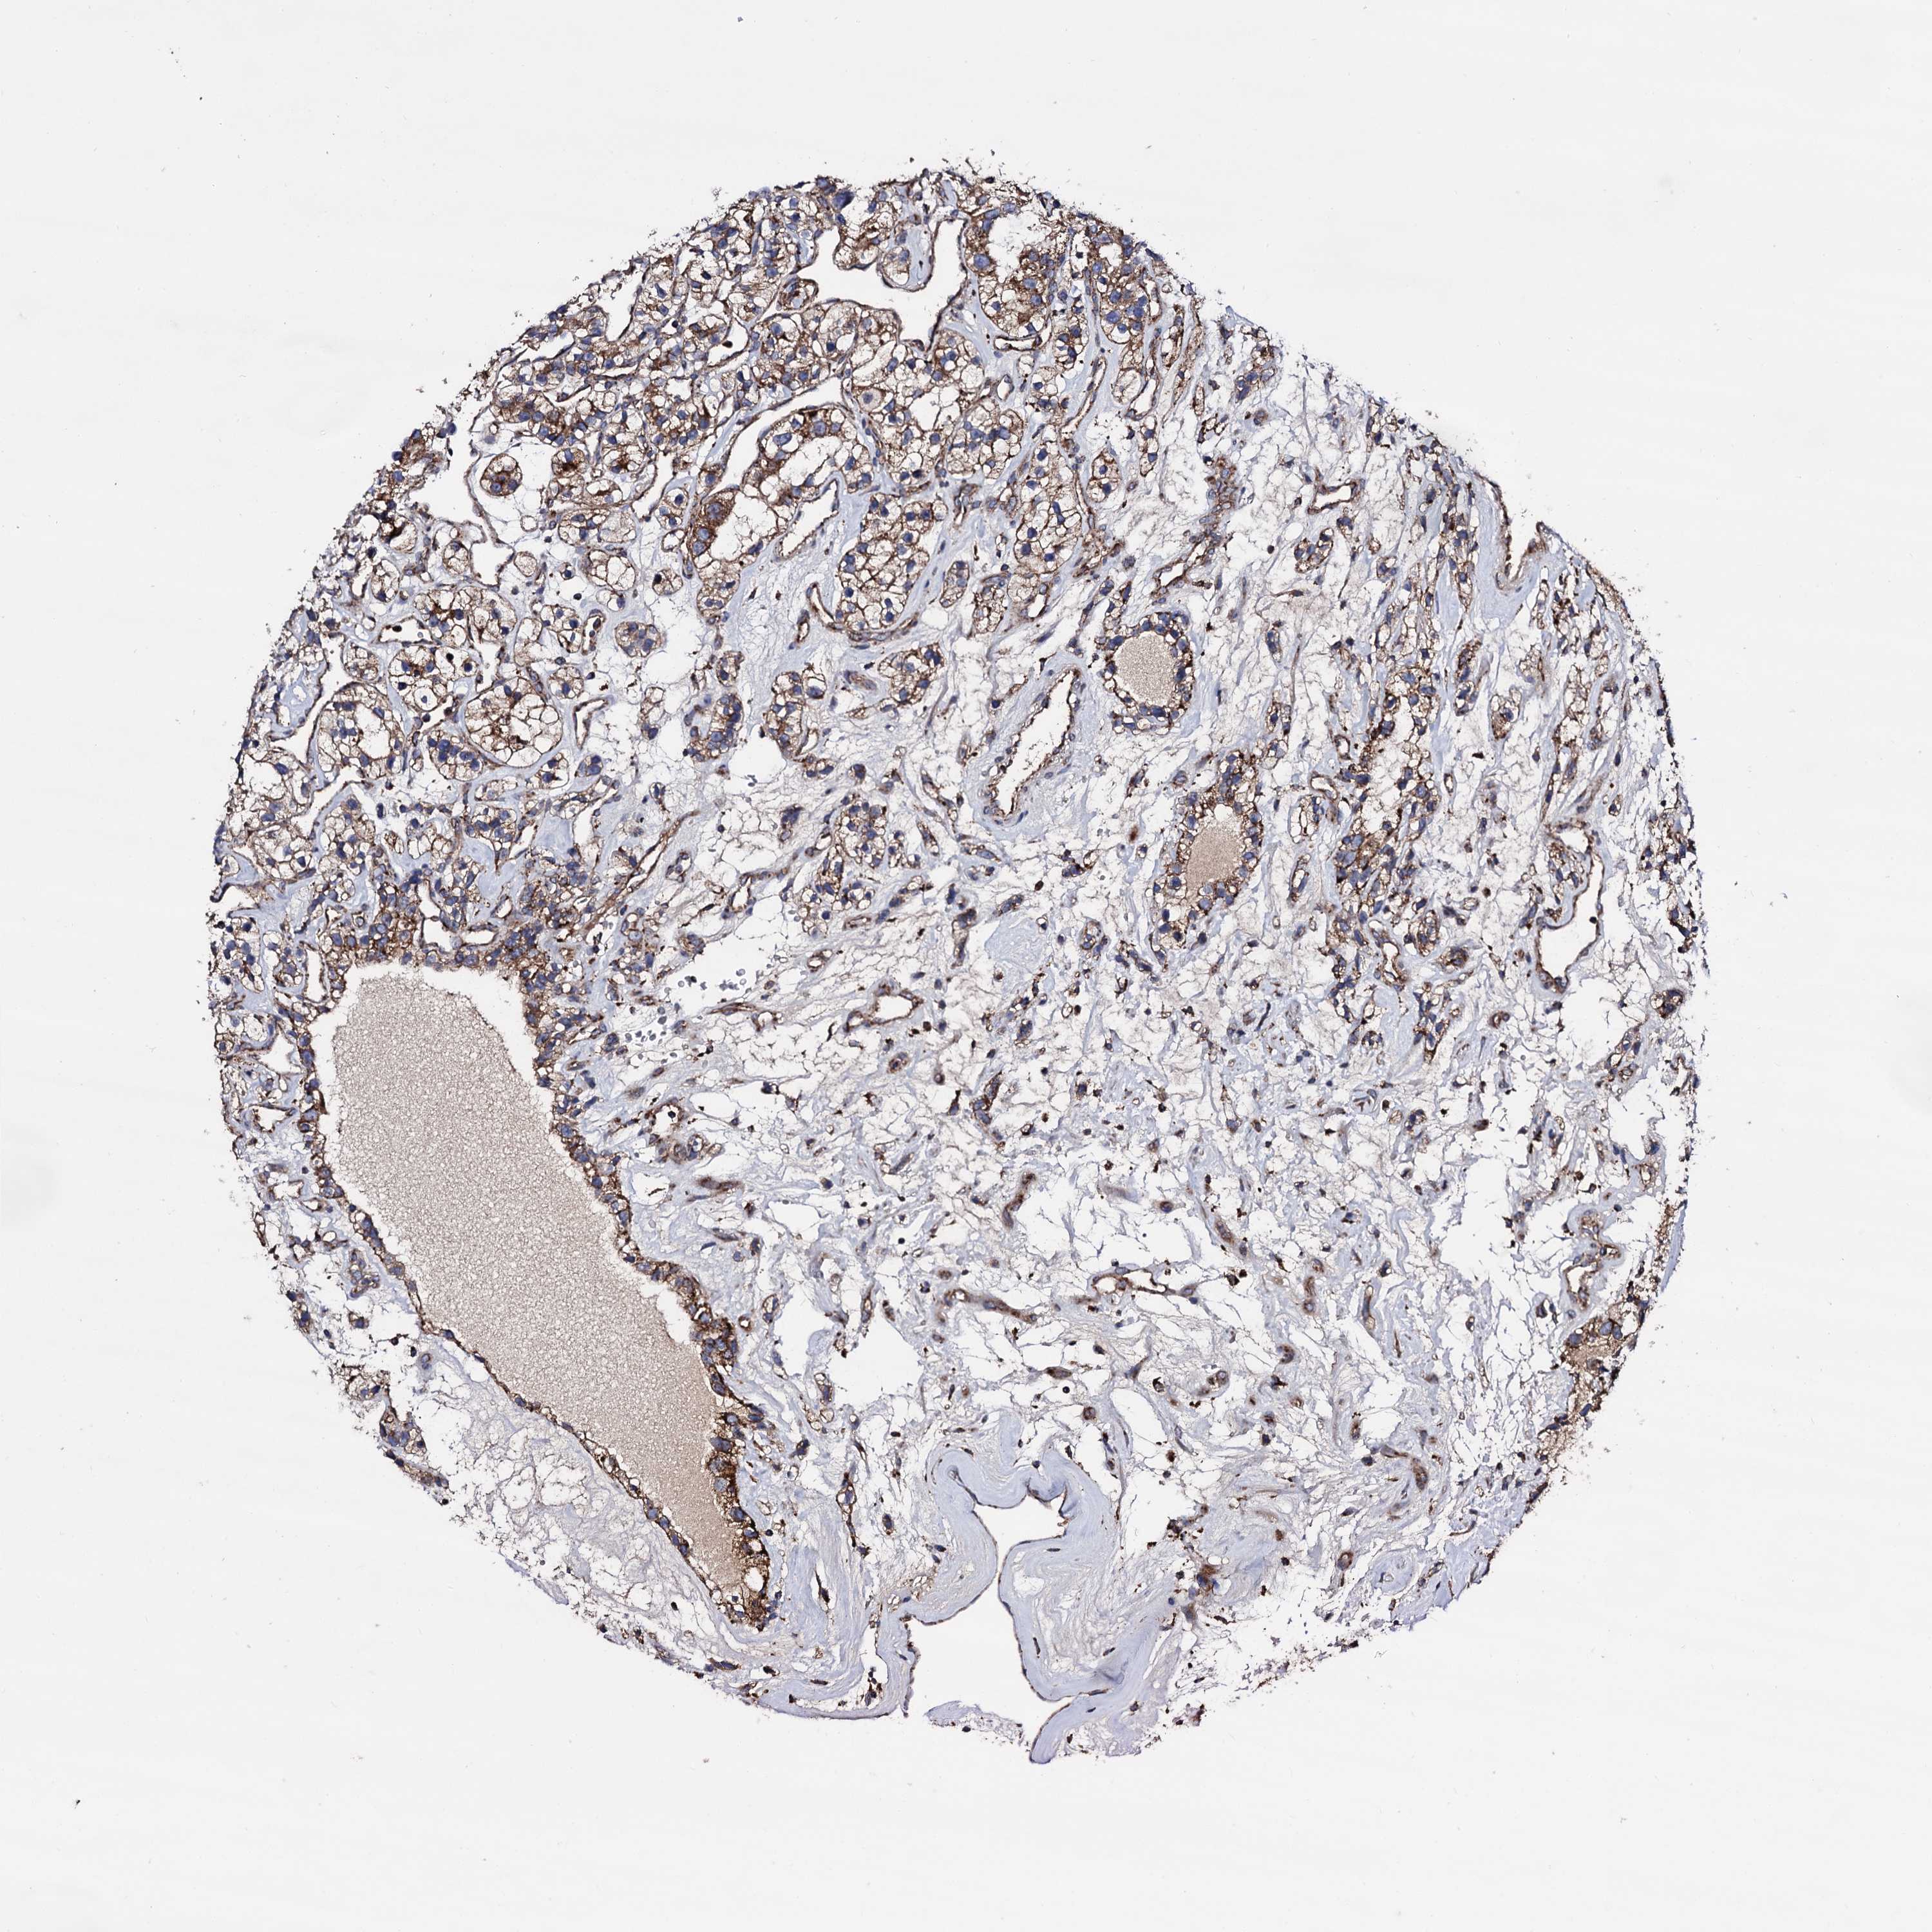

KIDNEY RENAL CLEAR CELL CARCINOMA (VALIDATION) - Interactive survival scatter ploti

The Survival Scatter plot shows the clinical status (i.e. dead or alive) for all individuals in the patient cohort, based on the same data that underlies the corresponding Kaplan-Meier plots. Patients that are alive at last time for follow-up are shown in blue and patients who have died during the study are shown in red.

The x-axis shows the expression levels (FPKM) of the investigated gene in the tumor tissue at the time of diagnosis. The y-axis shows the follow-up time after diagnosis (years). Both axes are complimented with kernel density curves demonstrating the data density over the axes. The top density plot shows the expression levels (FPKM) distribution among dead (red) and alive patients (blue). The right density plot shows the data density of the survived years of dead patients with high and low expression levels respectively, stratified using the cutoff indicated by the vertical dashed line through the Survival Scatter plot. This cutoff is automatically defined based on the FPKM cutoff that minimizes the p-score. The cutoff can be changed by dragging the vertical line or by entering a cutoff value in the square labeled "Current cut-off".

Under the Survival Scatter plot the p-score landscape (black curve; left axis) is shown together with dead median separation (red curve; right axis). Dead median separation is the difference in median mRNA expression between patients who have died with high and low expression, respectively. It is calculated as follows: median FPKM expression of dead patients with high expression - median FPKM expression of dead patients with low expression. This is intended to aid the user in visually exploring custom cutoffs and the associated p-scores and dead median separation.

Individual patient data is displayed and can be filtered by clicking on one or more of the category buttons on the top of the page. Categories describing expression level and patient information include: high, low, alive, dead, female, male and tumor stages. The scale of the x-axis can be toggled between linear and log-scale by clicking on the "x log" button. Mouse-over function shows TCGA ID, patient information and mRNA expression (FPKM) for each patient.

& Survival analysisi

Kaplan-Meier plots summarize results from analysis of correlation between mRNA expression level and patient survival. Patients were divided based on level of expression into one of the two groups "low" (under cut off) or "high" (over cut off). X-axis shows time for survival (years) and y-axis shows the probability of survival, where 1.0 corresponds to 100 percent.

IQCH is not prognostic in Kidney Renal Clear Cell Carcinoma (validation)

Best expression cut offi

Based on the FPKM value of each gene, patients were classified into two groups and association between prognosis (survival) and gene expression (FPKM) was examined. The best expression cut-off refers the FPKM value that yields maximal difference with regard to survival between the two groups at the lowest log-rank P-value. Best expression cut-off was selected based on survival analysis .

When clicking on this number, the vertical dashed line indicating cut-off, the interactive survival plot, and the Kaplan-Meier curve will be adjusted to show results based on the best expression cut-off.

: 0.77

TCGA RNA samplesi

RNA-seq data is reported as average FPKM (number Fragments Per Kilobase of exon per Million reads), generated by the The Cancer Genome Atlas (TCGA) .

Normal distribution across the dataset is visualized with box plots, shown as median and 25th and 75th percentiles. Points are displayed as outliers if they are above or below 1.5 times the interquartile range. FPKM values of the individual samples are presented next to the box plot.

Average pTPM 1.4

Number of samples 100